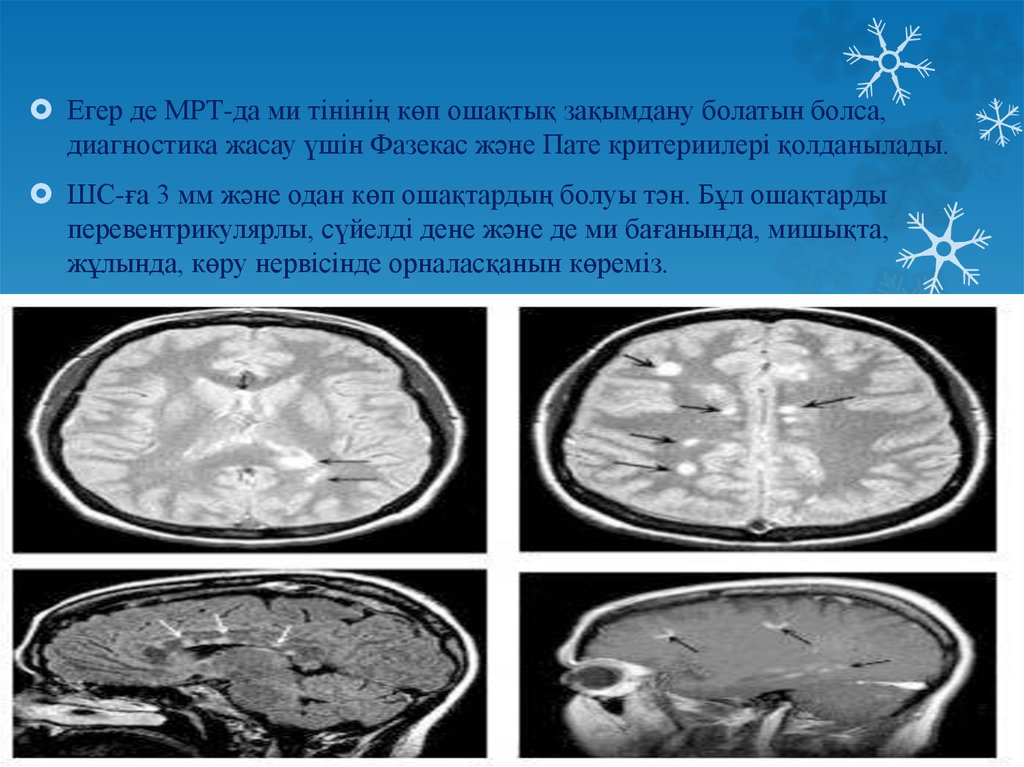

Fazekas grades. Мультифокальная лейкоэнцефалопатия. Резидуальная энцефалопатия на мрт. Прогрессирующая мультифокальная лейкоэнцефалопатия кт. Гипертензионная энцефалопатия на мрт.

Fazekas grades. Мультифокальная лейкоэнцефалопатия. Резидуальная энцефалопатия на мрт. Прогрессирующая мультифокальная лейкоэнцефалопатия кт. Гипертензионная энцефалопатия на мрт.